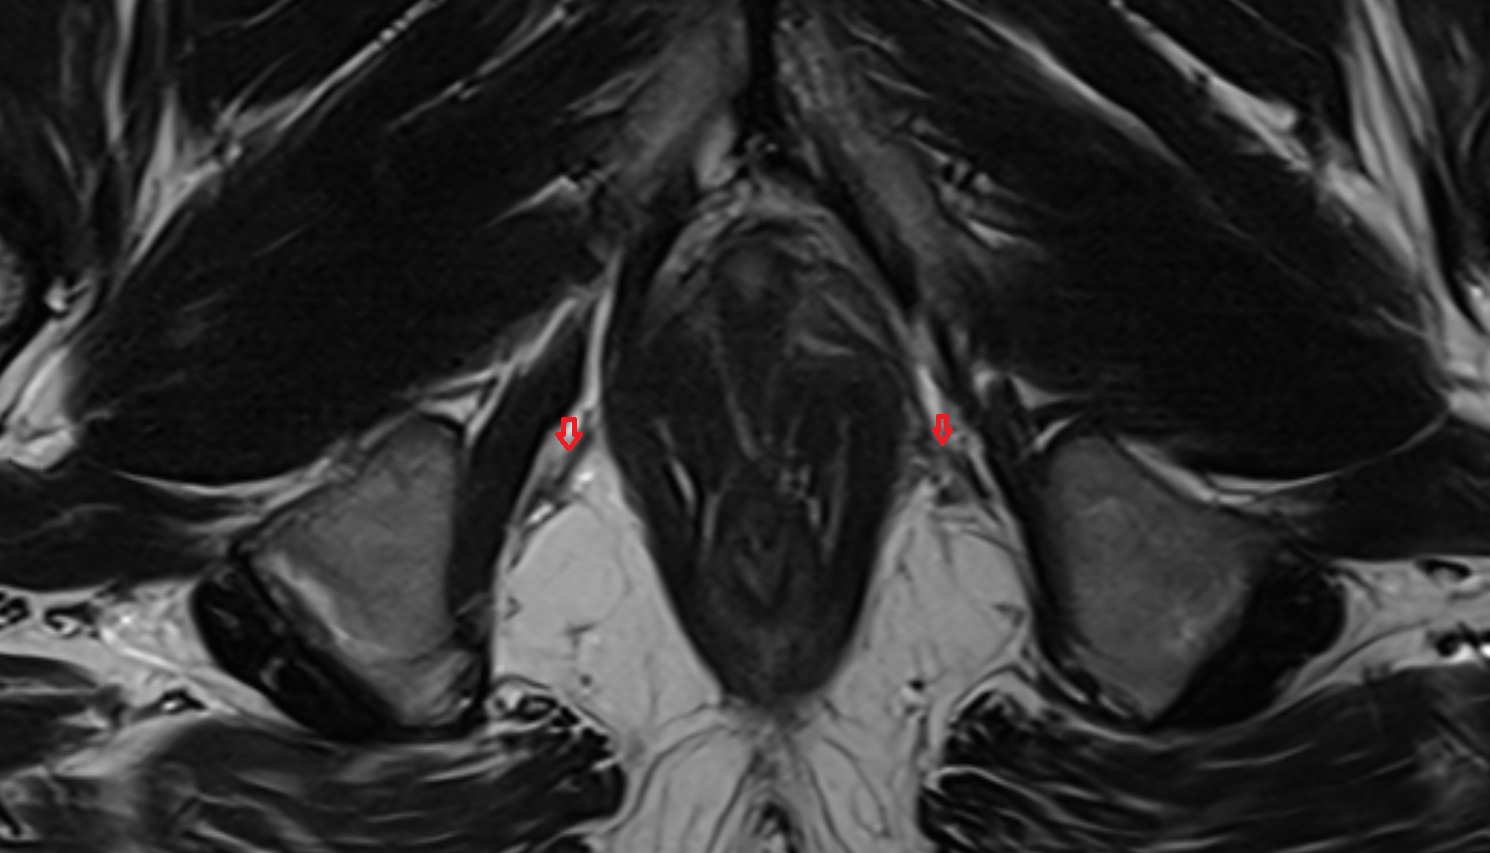

- Peripheral zone of prostate

- Anterior Fibromuscular Stroma of prostate

- Central zone of prostate

- Transitional zone of prostate